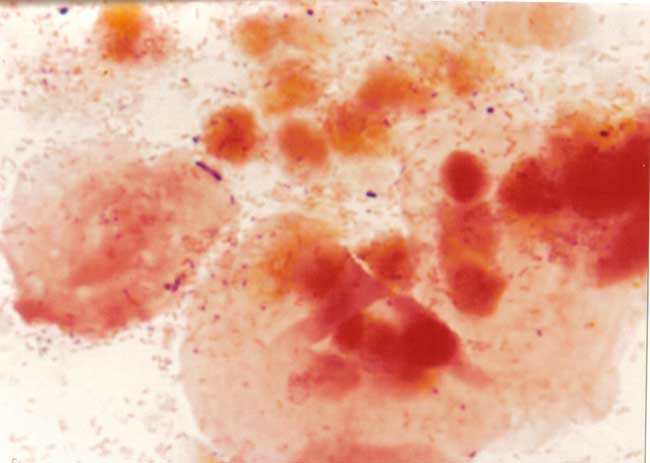

Una vagina saludable contiene muchos microorganismos, uno de los más comunes es el Lactobacillus acidophilus (LA).[5] El LA evita que otros microorganismos vaginales se reproduzcan a un nivel en donde pudiesen causar síntomas. Los microorganismos relacionados con la VB incluyen Gardnerella vaginalis, Mobiluncus, Bacteroides y Mycoplasma. Por razones desconocidas el número de estos organismos crecen con la VB mientras el número de organismos LA baja.